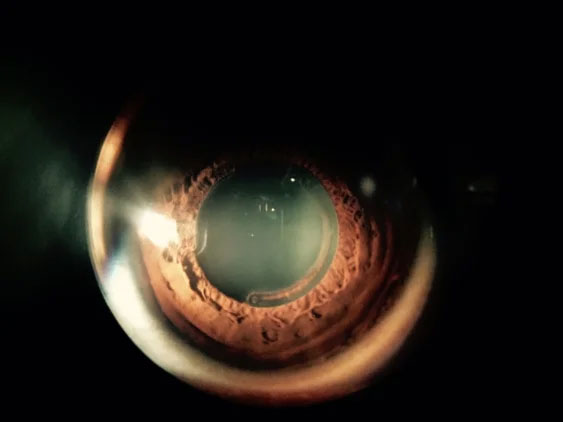

Keratoconus is an eye condition in which the shape of the cornea becomes distorted.

Keratoconus is an eye condition in which the shape of the cornea becomes distorted. The cornea is a clear structure that covers the front of the eye and allows light to enter the eye. In a healthy eye, the cornea curves like a dome. In an eye with keratoconus, the center of the cornea slowly thins and bulges so that it sags and has a cone shape.

Keratoconus can usually be diagnosed with a slit-lamp examination as well measurement of the corneal curvature. Your optometrist will look for signs such as corneal thinning, stress lines, and scarring at the apex of the corneal cone. Keratoconus, especially in the early stages, can be difficult to diagnose and its symptoms could be associated with other eye problems. Simply recognizing symptoms does not by itself diagnose the condition.